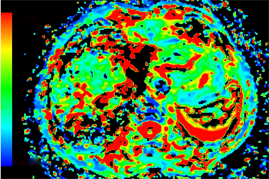

Figure 1. Axial MRI images of HCC patient before TACE treatment. (a) T1-weighted unenhanced image shows a hypointensive lesion in right lobe of liver. (b) Arterial phase contrast-enhanced image shows a heterogeneous enhanceed lesion. (c) ADC map. (d) Dslow map. (e) Dfast map. (f) f map.